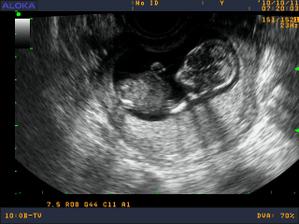

Moje brusko od zaciatku do konca

zacinam 11 tyzdnom, a vykukajucim pupikom